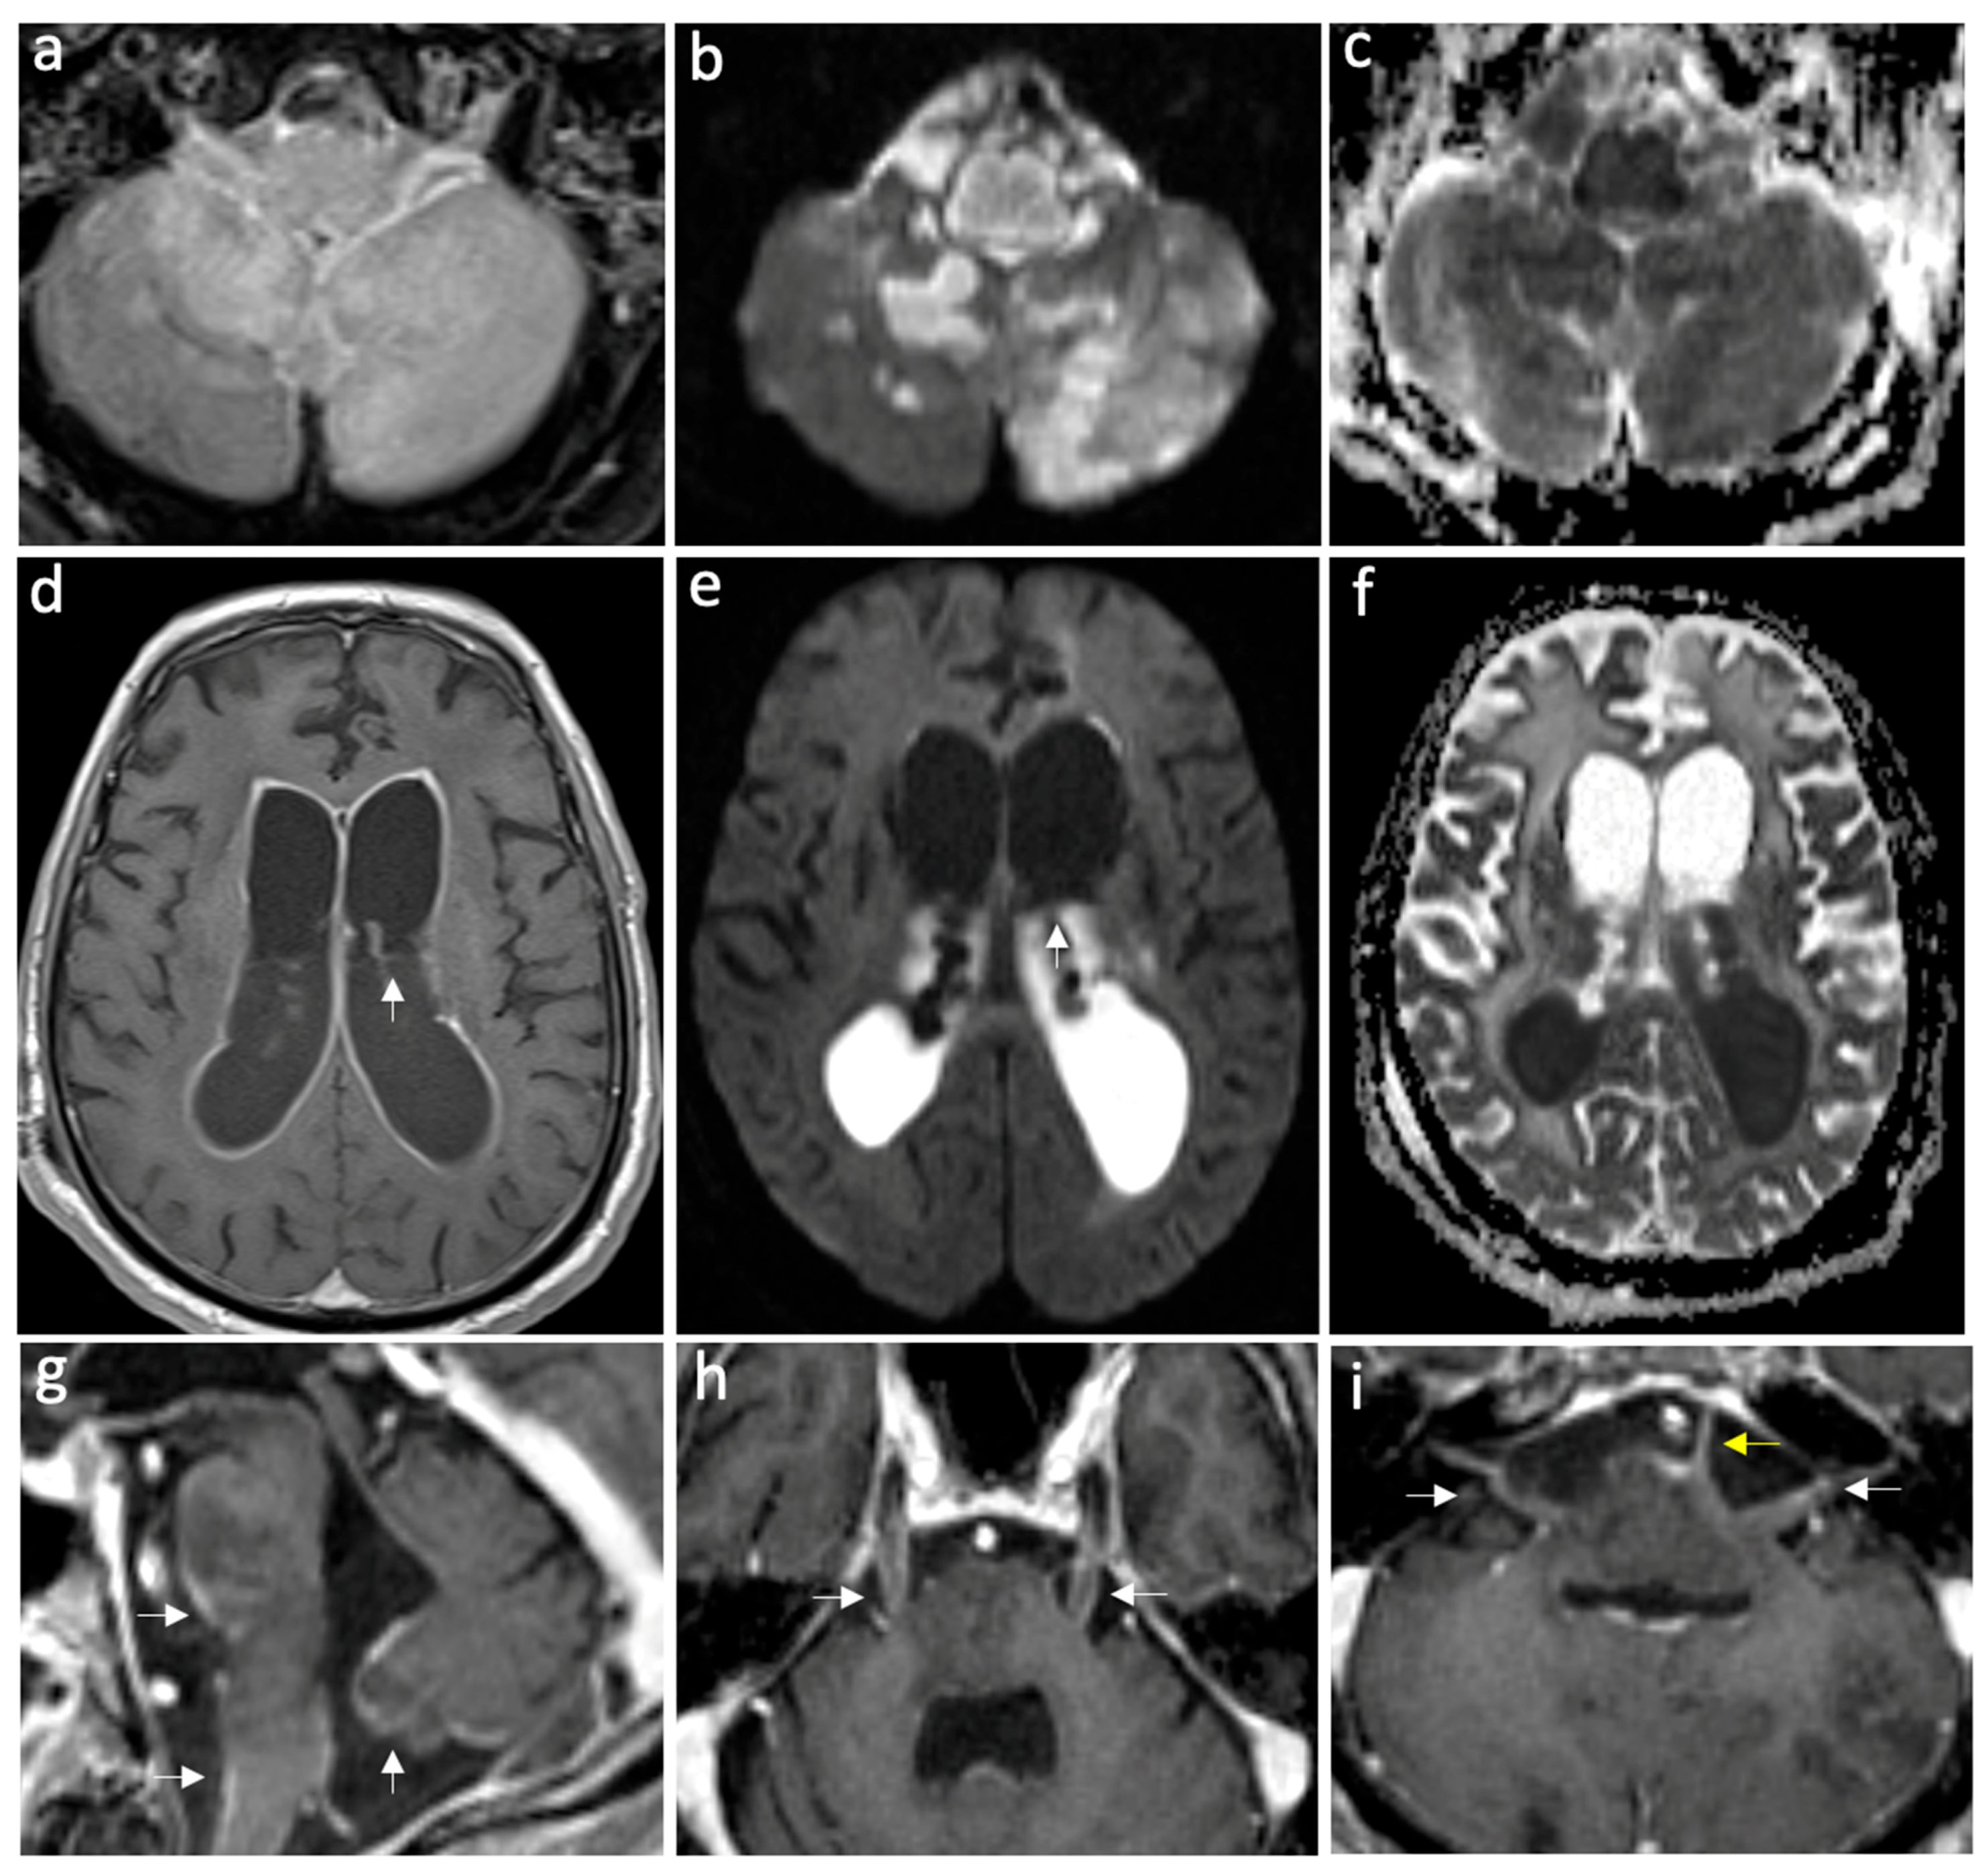

Figure 2.

Case of complicated meningoencephalitis with ventriculitis and empyema secondary to Salmonella enterica. Axial FLAIR post-gad (a), DWI, and ADC map (b,c) show abnormal parenchymal hyperintensities and diffusion restriction in the medulla oblongata and bilateral cerebellar hemispheres, consistent with encephalitis. Furthermore, note the restricted diffusion in the prepontine cistern, consistent with empyema. Axial T1 post-gadolinium (d), DWI, and ADC map (e,f) show intense ventricular ependymal surface enhancement related to ventriculitis and intraventricular diffusion restriction due to intra-ventricular empyema, with a pus fluid level indicated by white arrows. On the sagittal post-gadolinium image (g), leptomeningeal enhancement is visible on the ventral pons, medulla oblongata, and inferior vermis, indicating meningitis (white arrows). The axial post-gadolinium images show leptomeningeal enhancement along the bilateral trigeminal nerves (h), bilateral facial and vestibulocochlear nerves (white arrows), and the left abducent nerve (yellow arrow) (i).